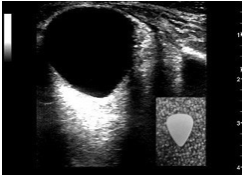

Imaging: FAST, further imaging as indicated by injuries/suspicion of clinician. Imaging should not be delayed or deferred 2/2 concern for fetal radiation exposure in the trauma setting!!!!